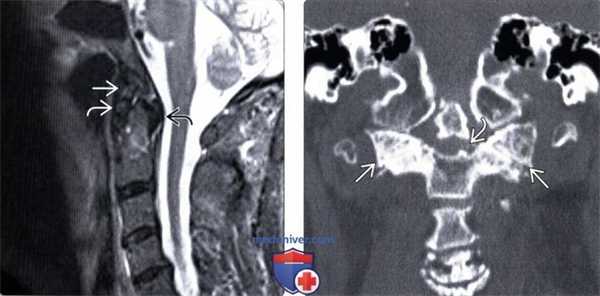

(Слева) На рентгенограмме зубовидного отростка в прямой проекции через открытый рот видны признаки остеоартроза (ОА) правого атлантоаксиального сустава в виде выраженного сужения суставной щели и формирования крупного остеофита. Обратите внимание, что суставная щель сужена неравномерно, в большей степени выражено сужение в наружном отделе сустава. Сравните этот сустав с противоположным нормальным сочленением.

(Справа) КТ, аксиальный срез: признаки выраженного дегенеративного поражения атлантодентального сочленения в виде сужения суставной щели, формирования небольших субхондральных кист, склероза и остеофитов. Также видны гипертрофические костные изменения на фоне ОА атлантоаксиального сустава. (Слева) КТ, фронтальный срез: случай выраженного дегенеративного поражения атлантоаксиальных сочленений. Поражены оба атлантоаксиальных сочленения, однако поражение это асимметрично (слева > справа). Значительные в размерах остеофиты (слева) видны как со стороны медиального, так и латерального края сустава.

(Справа) КТ, сагиттальный срез: случай тяжелою дегенеративного поражения латерального атлантоаксиального сочленения. Суставная щель его значительно сужена, имеет место выраженный склероз, изменение формы суставных поверхностей и формирование остеофитов. Обратите внимание на снижение высоты боковой массы атланта.